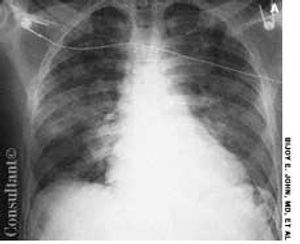

A 58-year-old man with a history of a seizure disorder was hospitalized with acute-onset shortness of breath immediately following a tonic-clonic seizure. He was afebrile; in respiratory distress; and hypoxic, with an oxygen saturation of 84% on room air. Auscultation revealed bibasilar crackles and an S3 gallop. The patient was given noninvasive mechanical ventilatory support, oxygen, and diuretics.